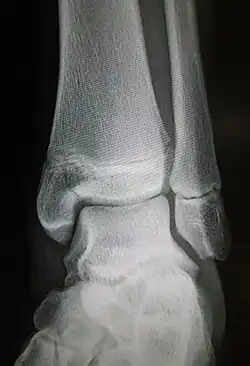

Radiograph showing a Maisonneuve fracture of the proximal fibula | |

The Maisonneuve fracture is a spiral fracture of the proximal third of the fibula associated with a tear of the distal tibiofibular syndesmosis and the interosseous membrane. There is an associated fracture of the medial malleolus or rupture of the deep deltoid ligament of the ankle. This type of injury can be difficult to detect.[1][2]